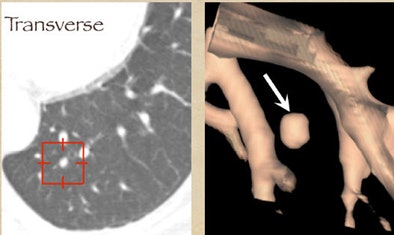

One example, a nodule that looked like an adjacent vessel in the transverse plane, was seen clearly as a lung nodule in coronal, sagittal, and volume-rendered views. "I'm quite certain that the LIDC group is missing nodules because of the limitation of only transverse section presentation," Rubin said.

| CT finding (left) has the appearance of an adjacent vessel in transverse-section reconstruction and was not called by any of the four LIDC readers. After viewing transverse, coronal, sagittal, and volume-rendered reconstructions (right), all four university readers called the finding a lung nodule. |